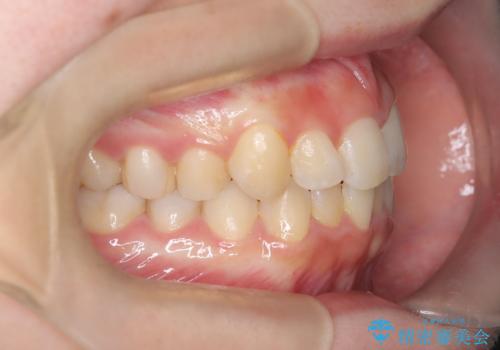

- 右上の前歯(2番)が下の歯より内側に入っている反対咬合を主訴にご来院されました。精密な検査の結果、この反対咬合を解消するためには、右上の歯列に前歯を出すためのスペースを確保する必要があると判明しました。患者様のご希望に合わせ、透明で目立たないインビザライン(マウスピース矯正)による治療計画を立案。奥歯全体を奥へ動かす遠心移動でスペースを作り、反対咬合を解消することを目指します。

今回の矯正治療では、透明なマウスピース型の装置インビザラインを使用しました。治療は、緻密なデジタル計画に基づき、奥歯から順に歯列全体を後方へ移動させる遠心移動を実施し、前歯を前に出すためのスペースを確保しました。このスペースを利用して、内側に入り込んでいた右上2番をスムーズに前方に誘導し、正常な咬み合わせへと改善。目立たないインビザラインで、機能的な咬み合わせと美しい前歯の並びを獲得していただけました。